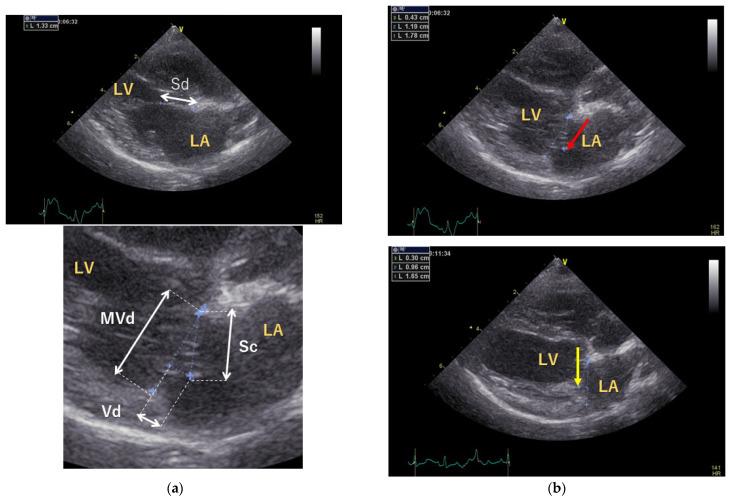

Background: Detailed surgical techniques for treating canine mitral regurgitation have not been previously reported. Method: This case series included six consecutive client-owned dogs with mitral regurgitation. All dogs underwent a combined protocol, including the modified loop technique and De Vega annuloplasty (MODEL surgery), in 2021. Artificial loops covering 80% of the length of the strut chordae tendineae were used for chordal replacement. Mitral annuloplasty was subjectively performed, targeting the circumference of the septal leaflet. Results: The breeds were Chihuahua-mixed breed, Spitz, Pomeranian, Cavalier King Charles Spaniel, and Chihuahua, with average ages and weights of 11.4 ± 2.3 years and 5.49 ± 2.98 kg, respectively. The aortic cross-clamp, pumping, and surgery times were 64.0 ± 7.5 min, 168.5 ± 39.1 min, and 321.0 ± 53.1 min, respectively. After MODEL surgery, left atrial-to-aortic ratios significantly decreased from 2.20 ± 0.18 to 1.26 ± 0.22 (p < 0.01), and left ventricular end-diastolic internal diameter normalized to body weight significantly decreased from 2.03 ± 0.26 to 1.48 ± 0.20 (p < 0.01). In all cases, the clinical signs disappeared or improved significantly. Conclusions: MODEL surgery increased mitral valve coaptation, normalized heart sizes, and significantly improved clinical signs in dogs with mitral regurgitation.

背景

此前尚未报道过治疗犬二尖瓣反流的详细手术技术。方法:本病例系列包括6只连续的家养患二尖瓣反流的犬。所有犬于2021年接受了包括改良袢环技术和德维加瓣环成形术(MODEL手术)的联合方案。使用覆盖腱索长度80%的人工袢进行腱索置换。二尖瓣瓣环成形术主观上针对间隔叶的周长进行。结果:品种包括吉娃娃混血、博美犬、波美拉尼亚犬、骑士查理王小猎犬和吉娃娃,平均年龄和体重分别为11.4±2.3岁和5.49±2.98千克。主动脉阻断、体外循环和手术时间分别为64.0±7.5分钟、168.5±39.1分钟和321.0±53.1分钟。MODEL手术后,左心房与主动脉比值从2.20±0.18显著降至1.26±0.22(p<0.01),左心室舒张末期内径与体重的比值从2.03±0.26显著降至1.48±0.20(p<0.01)。在所有病例中,临床症状消失或显著改善。结论:MODEL手术增加了二尖瓣的对合,使心脏大小恢复正常,并显著改善了二尖瓣反流犬的临床症状。